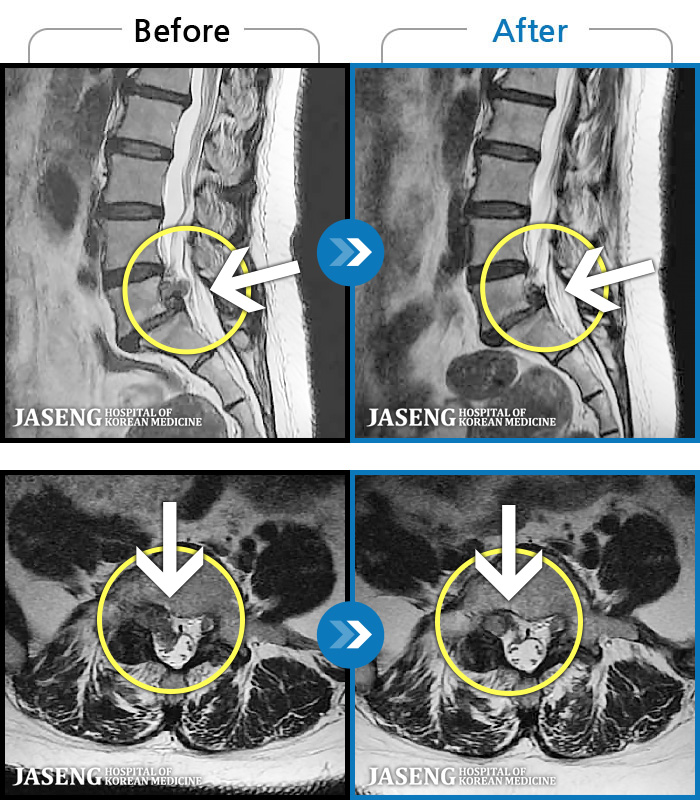

[Կñ:24.06.08~24.08.31]

[_㸮ũ] ġ ٸ ſ ؿ.

No.117

ȸ 497

2024.12.24